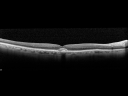

95-year-old man was seen in the office on November 14, 2011. He was in for a comprehensive evaluation with you recently and you saw a spot in his macula and suggest he come here for an evaluation. He is in excellent health and he doesn’t notice a vision problem. He had ReSTOR intraocular lenses done at a local large ophthalmology practice. VISUAL ACUITY: OD 20/32, OS 20/80. IOP: OD 11, OS 7. SLIT EXAMINATION: ReSTOR intraocular lenses in good position in both eyes. EXTENDED OPHTHALMOSCOPY: OD: Vertical C/D ratio is 0.3. There is no posterior vitreous separation. There is an 800 micron yellow pigment spot under the fovea. OS: Vertical C/D ratio is 0.3. There is no posterior vitreous separation. There is an 800 micron yellow pigment spot under the fovea. SPECTRALIS-SD-OCT SCAN: The OCT scan shows pigment epithelium thickening in each eye. There is no intraretinal or subretinal fluid. Photos confirm clinical findings. IMPRESSION: 1. PATTERN DYSTROPHY TYPE MACULAR DEGENERATION – BOTH EYES

Pattern Dystrophy - Adult Vitelliform - 95 Year Old Man with Good Vision595 views95-year-old man in excellent health and he doesn’t notice a vision problem. OD 20/32, OS 20/8000000